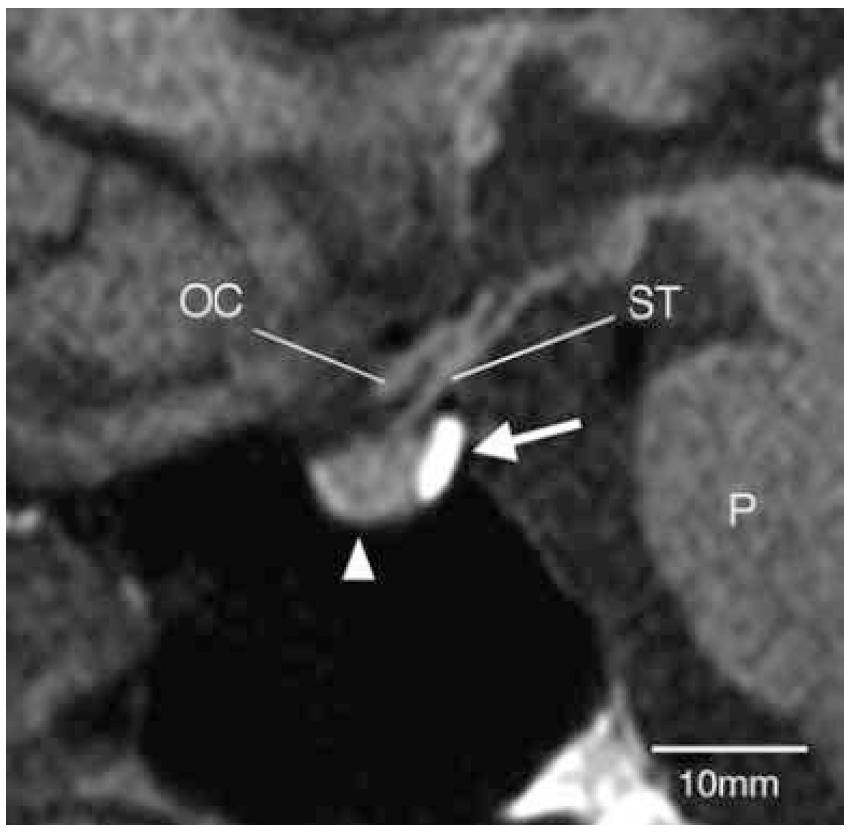

Рис. 1. Вид гипоталамо-гипофизарной области в норме.

При ЦНД интенсивность характерного сигнала от нейрогипофиза, как правило, отсутствует в результате нарушения синтеза, транспорта или хранения нейросекреторных гранул (рис. 2). В некоторых случаях наследственного ЦНД сигнал от задней доли сохраняется, что выявляется очень редко и составляет менее 5% общего числа пациентов с ЦНД.

Рис. 2. Вид гипоталамо-гипофизарной области при ЦНД.

Для гипофизита характерно значительное утолщение ножки гипофиза, которая после контрастного усиления приобретает гиперинтенсивный сигнал на Т1ВИ (рис. 3). Дифференциальная диагностика проводится с феноменом «застаивания», который оценивается на Т1ВИ без контрастного усиления.

Рис. 3. МР-картина лимфоцитарного гипофизита.

Феномен «застаивания» («dummimg-up» phenomenon) описан при объемных образованиях хиазмально-селлярной области, сдавливающих ножку гипофиза. Он проявляется отсутствием сигнала от нейрогипофиза и гиперинтенсивным сигналом от ножки гипофиза за счет скопления в ней везикул с AVP. При этом, как правило, ножка гипофиза берет на себя функции его задней доли, и клиническая картина ЦНД не развивается [1, 19].

Формирование эктопической задней доли гипофиза – хорошо известный феномен, развивающийся через довольно продолжительное время после перерезки ножки гипофиза. При этом ткань проксимального конца ножки увеличивается в размерах и реорганизуется в эктопическую заднюю долю, которая секретирует AVP подобно нормальному нейрогипофизу. Чаще всего эктопическая задняя доля формируется, когда ножка пересечена близко к гипофизу, если же пересечение ножки происходит около гипоталамуса, то ее образование наблюдается редко. При МРТ эктопическая задняя доля гипофиза визуализируется на Т1-взвешенных изображениях как небольшой узел с характерным гиперинтенсивным сигналом у проксимального конца пересеченной ножки гипофиза, причем адекватность секреторной функции эктопической доли коррелирует с ее размером, и при больших размерах ее функция восстанавливается полностью.